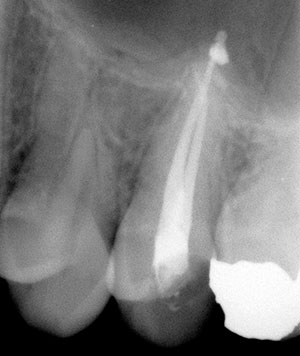

Uno de los tratamientos más utilizados en la clínica dental es la endodoncia o desvitalización. Se trata de extraer por completo la pulpa dental (nervio/s de la pieza), después se rellenaran los conductos con un cemento antibacteriano y unas puntas de resina. Esto permitirá conservar la pieza propia.

En Clínica Dental Amigo el procedimiento lo realiza un odontólogo especialista (endodoncista) con un motor especial de endodoncias que hace que se acorte sensiblemente el tiempo del tratamiento y se consigue un rango mayor de éxito en la eliminación de bacterias. Durante todo el tratamiento el endodoncista necesitara hacer alguna radiografía de control.

En nuestra clínica disponemos de radio visiografía digital (rvg), más rápida y con mucha menos radiación para el paciente que las radiografías manuales.